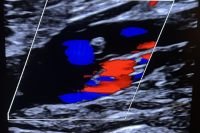

Penumbra Thrombectomy